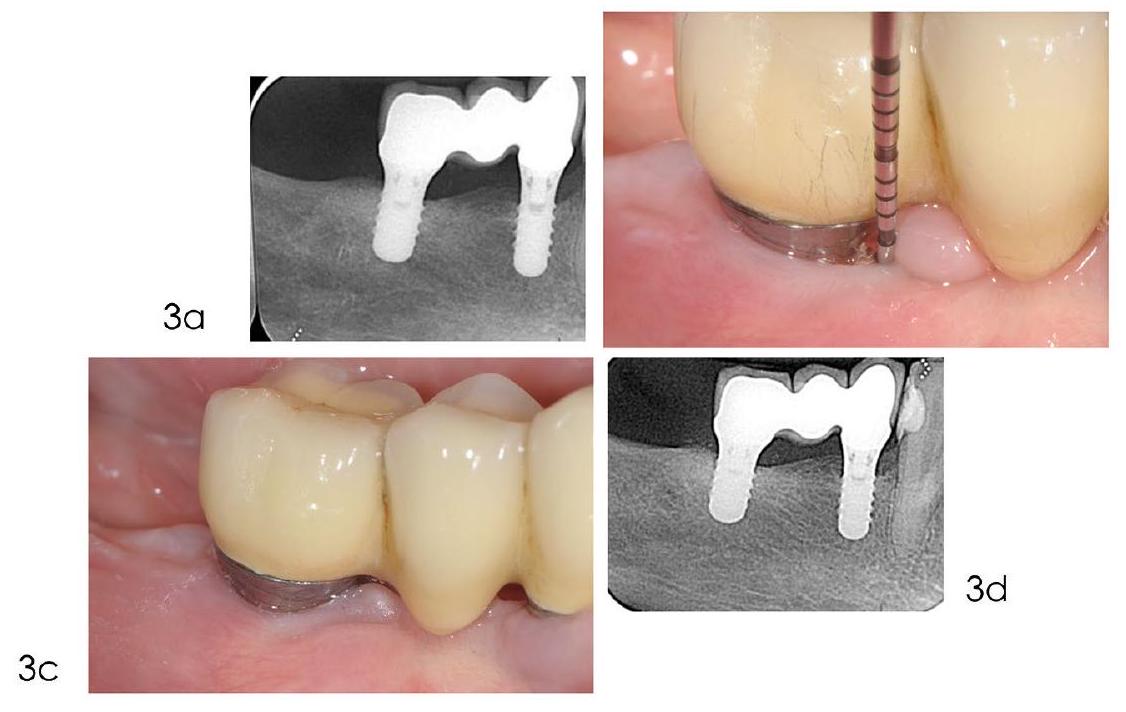

Indications and efficacy of reconstructive approaches

- The depth of the intrabony defect

- The defect configuration: ideally, an isolated three- or four-wall-contained defect

- Presence of a band of peri-implant keratinised mucosa.

The main objective of the XVIII European Workshop on Periodontology was to summarise the evidence-based recommendations for individual interventions used in the management of peri-implant

diseases, based on the best available evidence and/or expert consensus. For the guideline development process on the efficacy of bone reconstructive therapies in the management of peri-implantitis defects, a systematic review was conducted by Donos and co-workers.

- Deep and narrow defects are more favourable for the stabilisation of the graft and the consequent formation of new bone

- The extension of the full-thickness flap should be planned carefully, balancing the aim to minimise the invasiveness of the procedure and the need to have access to the bottom of the defect

- The regenerative biomaterial should be selected on the basis of proper scientific validation and applied without overfilling the defect

- The graft should be inserted only after complete elimination of the granulation tissue and the decontamination of the implant surface